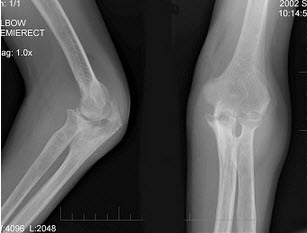

17、单项选择题

男,61岁,低烧,消廋,胸片示有结核病灶,结合图像,最可能诊断是()

A.肘关节结核

B.肘关节退行性变

C.骨折

D.未见异常

E.类风湿关节炎